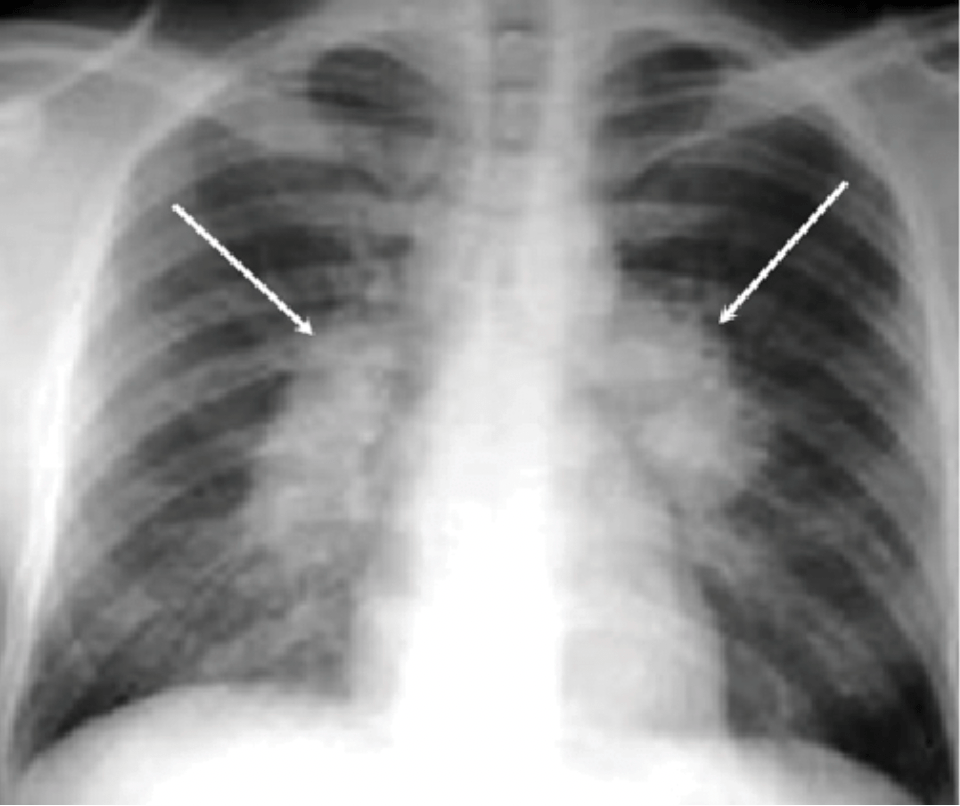

A 3 y/o patient who recently visited family in Mexico presents with 3 weeks of cough, weight loss, and feeling sweaty at night. This is the most common chest x-ray finding associated with this diagnosis.

What is hilar lymphadenopathy?

- CXR: hilar lymphadenopathy is classic

- Young children (<5 years) typically present with lymphadenopathy.

- Adolescents more frequently develop adult-type tuberculosis with upper lobe opacities and cavitation associated with sputum production.

- Pediatric TB is smear-negative up to 70% of the time (likely due to paucibacillary nature of lung lesions)

- Highest risk for miliary spread and CNS disease in young kids

- BCG vaccine does not rule out infection.